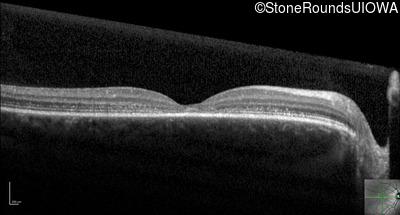

Optical Coherence Tomography - Right - 20/32

Exemplar / OCT Stack

Optical Coherence Tomography - Left - 20/20 -2